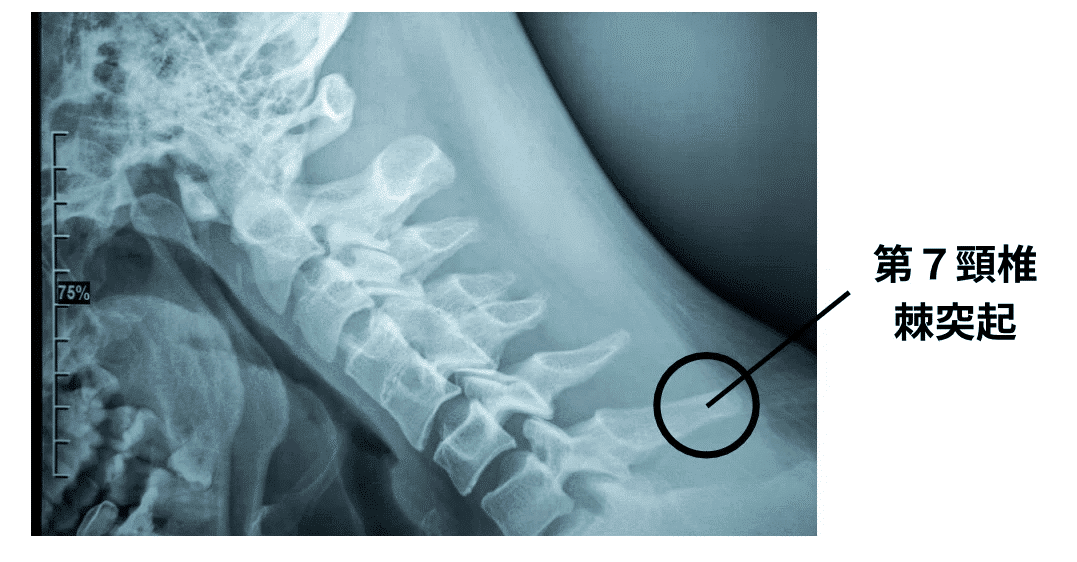

第7頚椎棘突起

椎体で最も突出する棘突起は一般的に第7頚椎(C7)とされ、隆椎(Vertebra prominens:VP)とも呼ばれています(図1)。

図1 頚椎のレントゲン画像